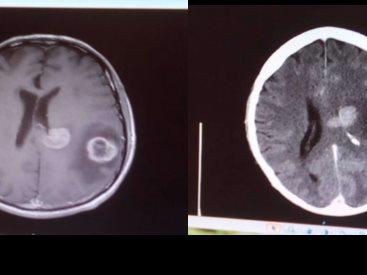

On Boxing Bay 2016 Tony was admitted to hospital with terrible headaches, loss of speech and weakness in the body. Tony underwent an urgent CT scan and MRI which showed up 2 very large tumours on the brain. The following day Tony have a more extensive CT scan which showed up 8 tumours. On the 30th December 2016 PN Hospital sent to Tony to Wellington Hospital to be seen by the Neuro Specialist. On New Year’s eve at 7pm Tony underwent Brain surgery to remove one of the easy tumours for Biopsy. The operation went well and was successful.